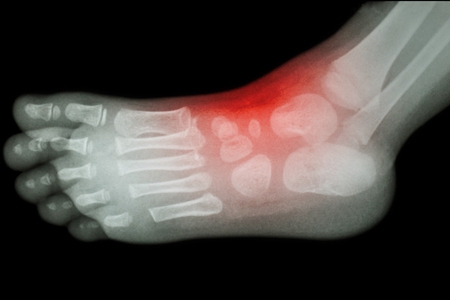

痛风石与慢性痛风关节炎期

随着间歇期的缩短,疼痛逐渐的加剧,受累关节也逐渐增多,持续的高尿酸水平导致了尿酸盐结晶析出并沉积在软骨,关节的滑膜、肌腱和多处软组织处形成痛风石。不断增多的痛风石及炎症的反复发作导致关节僵硬、活动受限乃至畸形。

发展至这一时期,痛风患者更应积极配合医生进行规范治疗。采用中医微创可视针刀镜洗下尿酸盐结晶清除溶解术,进行关节腔内清洗、剔除尿酸盐结晶,防止尿酸盐进一步沉积肾脏。接着免疫吸附疗法将血液中的尿酸清除掉、平衡尿酸,调理肾脏代谢,防止尿酸盐结晶二次沉积关节或是肾脏。